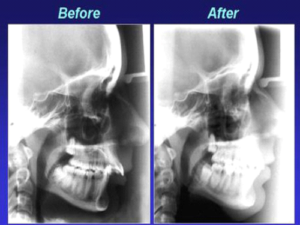

これを達成するために、下顎の後退した症例では、理想的には下顎骨前進手術やオトガイ形成手術が行われます。

それでは、下顎後退症例は、手術だけが適応でしょうか。

成長期であれば、もちろん機能的矯正装置により下顎の前進が少しはできるとされています。

下顎後退症例では、下顎骨前進手術と頤形成術が行われます。

手術ほどの変化は期待できないとしても成長期であれば、機能的顎矯正装置を用いて下顎を前方発育させることができます。